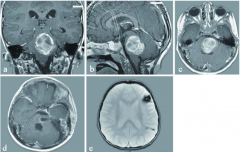

神经内镜治疗松果体区肿瘤患者

神经内镜干预目前被认为是一种替代治疗异质性组颅内肿瘤包括...